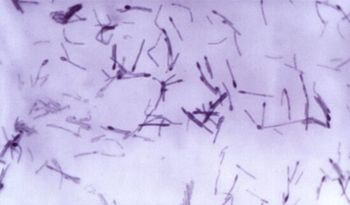

Discovered Clostridium toxin found in alfalfa cubes was causing serious illness and even death in horses